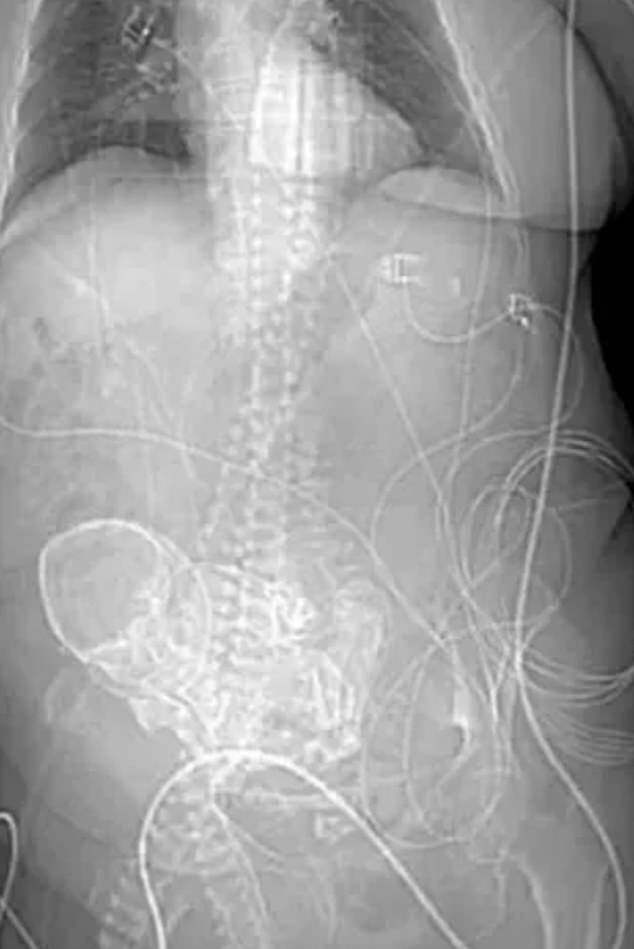

Пожилая дама из Бразилии пришла в больницу с жалобой на боли в животе. В результате сканирования врачи обнаружили в ее брюшной полости кальцифицированный плод — литопедион. Выяснилось, что окаменевший эмбрион находится там уже более пятидесяти лет.

До обнаружения литопедиона медики подозревали у женщины онкологию. После сканирования и разговора с пациенткой они пришли к выводу, что она носила в своём теле мёртвый плод с момента внематочной беременности, случившейся с ней в возрасте 25 лет.

Это редкое явление чаще всего происходит, когда плод погибает во время внематочной беременности и, будучи слишком большим для реабсорбции организмом, кальцинируется. Так материнский организм реагирует на инородное тело, защищая себя от мертвой ткани и предотвращая инфекцию.